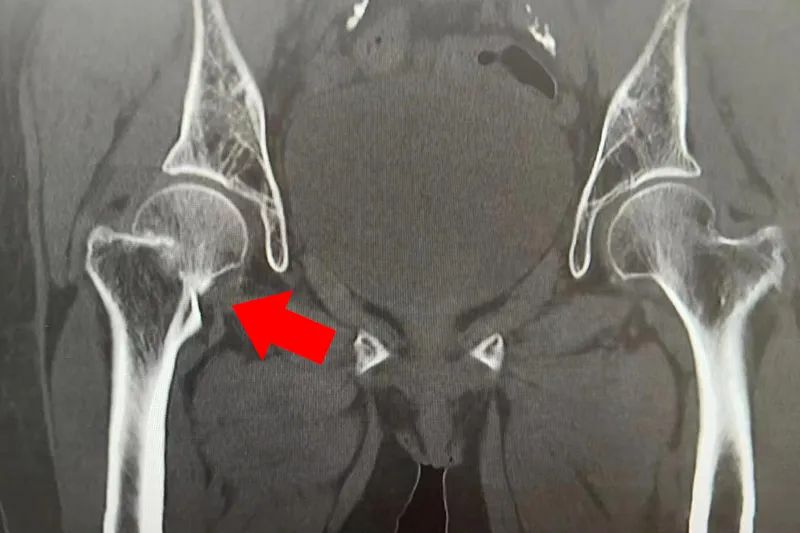

卢奶奶,今年75岁,在家中不幸从二楼坠落,右髋部、腰背部疼痛剧烈,右下肢活动严重受限,无法站立及下床,翻身困难。后被家人带至亳州骨科医院骨二科就诊。通过询问病史结合查体及影像学检查诊断为:

1.右侧股骨颈骨折

入院后,为了保障卢奶奶早日恢复肢体功能,经由骨二科医师专家团队联合会诊,建议行右侧人工股骨头置换手术治疗。

术前CT影像

人工股骨头置换术是我院骨科的一项常规手术,对于老年股骨颈骨折患者可耐受手术者行此手术,患者术后2-3天即可下床行走,有效避免了因长期卧床引起的并发症,为患者减轻了痛苦。